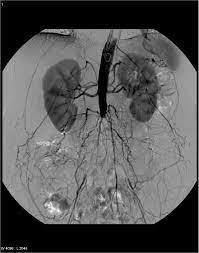

leriche syndrome (aorto-occlusive disease)

leriche syndrome